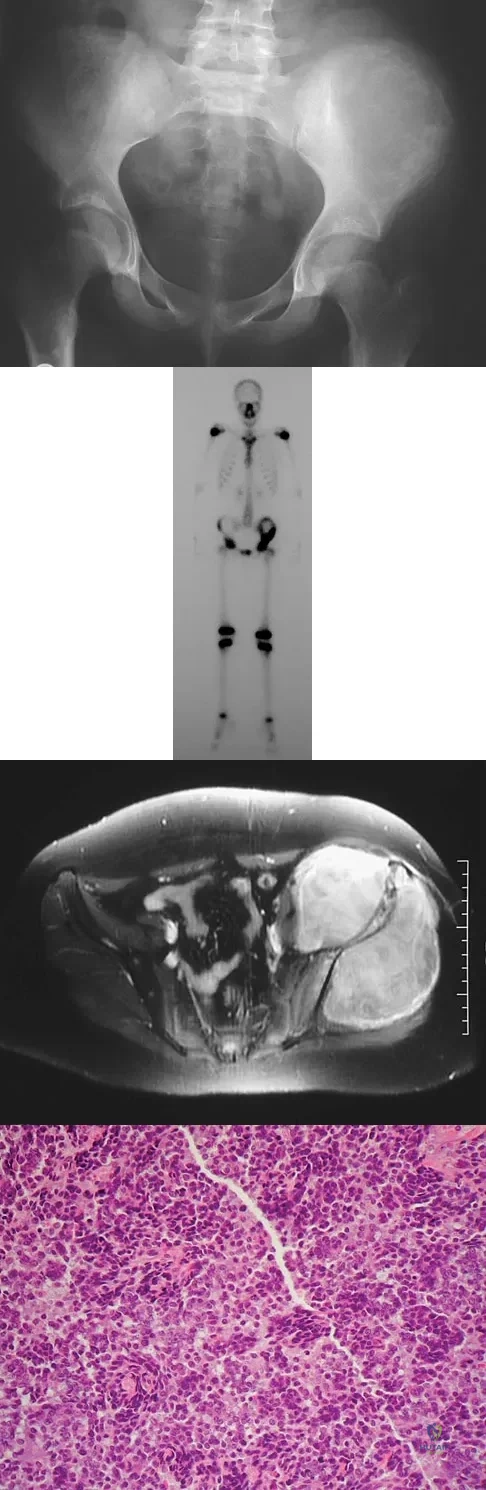

A 13-year-old girl has had increasing left hip pain for the past 4 months. A radiograph, bone scan, MRI scan, and photomicrograph are shown in Figures 1a through 1d. Which of the following immunohistochemistry results would confirm the most likely diagnosis?